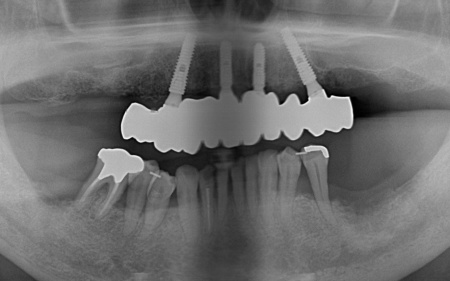

インプラント治療が可能かどうかを調べるためレントゲンとCTの撮影を実施したところ、インプラントを支えるのに十分な骨の量があり問題なく治療できることが確認できました。

①上の歯7本、右下の奥歯2本を抜歯する。上あごには抜歯と同時に4本のインプラントを埋め、その上に10本分の仮歯を取り付けるオールオンフォーを行う。

インプラントの種類には、あごの骨と結合する力に優れたオステム社のETⅢを採用。インプラントが骨にしっかり定着するまでの間は、通常のインプラントよりも細い暫間インプラントを一時的に併用して仮歯を支える

②インプラントが安定したことを確認してから、仮歯を外して最終的な人工歯を装着する